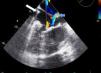

ETE: a) imagem anatómica normal; b) imagem correspondente mostrando ausência de continuidade entre a válvula aórtica e a válvula auriculoventricular esquerda (morfologicamente tricúspide), através de um infundíbulo (asterisco); ventrículo morfologicamente direito em posição esquerda e válvula aórtica em normal continuidade com vaso sistémico (aorta) (vídeo 2).

| Ventrículo morfologicamente direito (trabeculado), relacionado com válvula AV morfologicamente tricúspide em posição esquerda e em continuidade com válvula aórtica e aorta torácica (Figuras 2 e 3) |